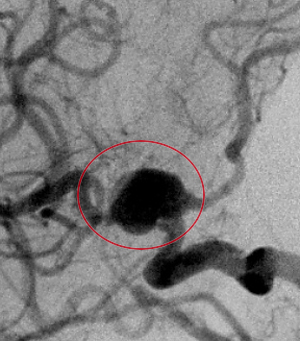

コイル塞栓手術前

コイル塞栓手術後